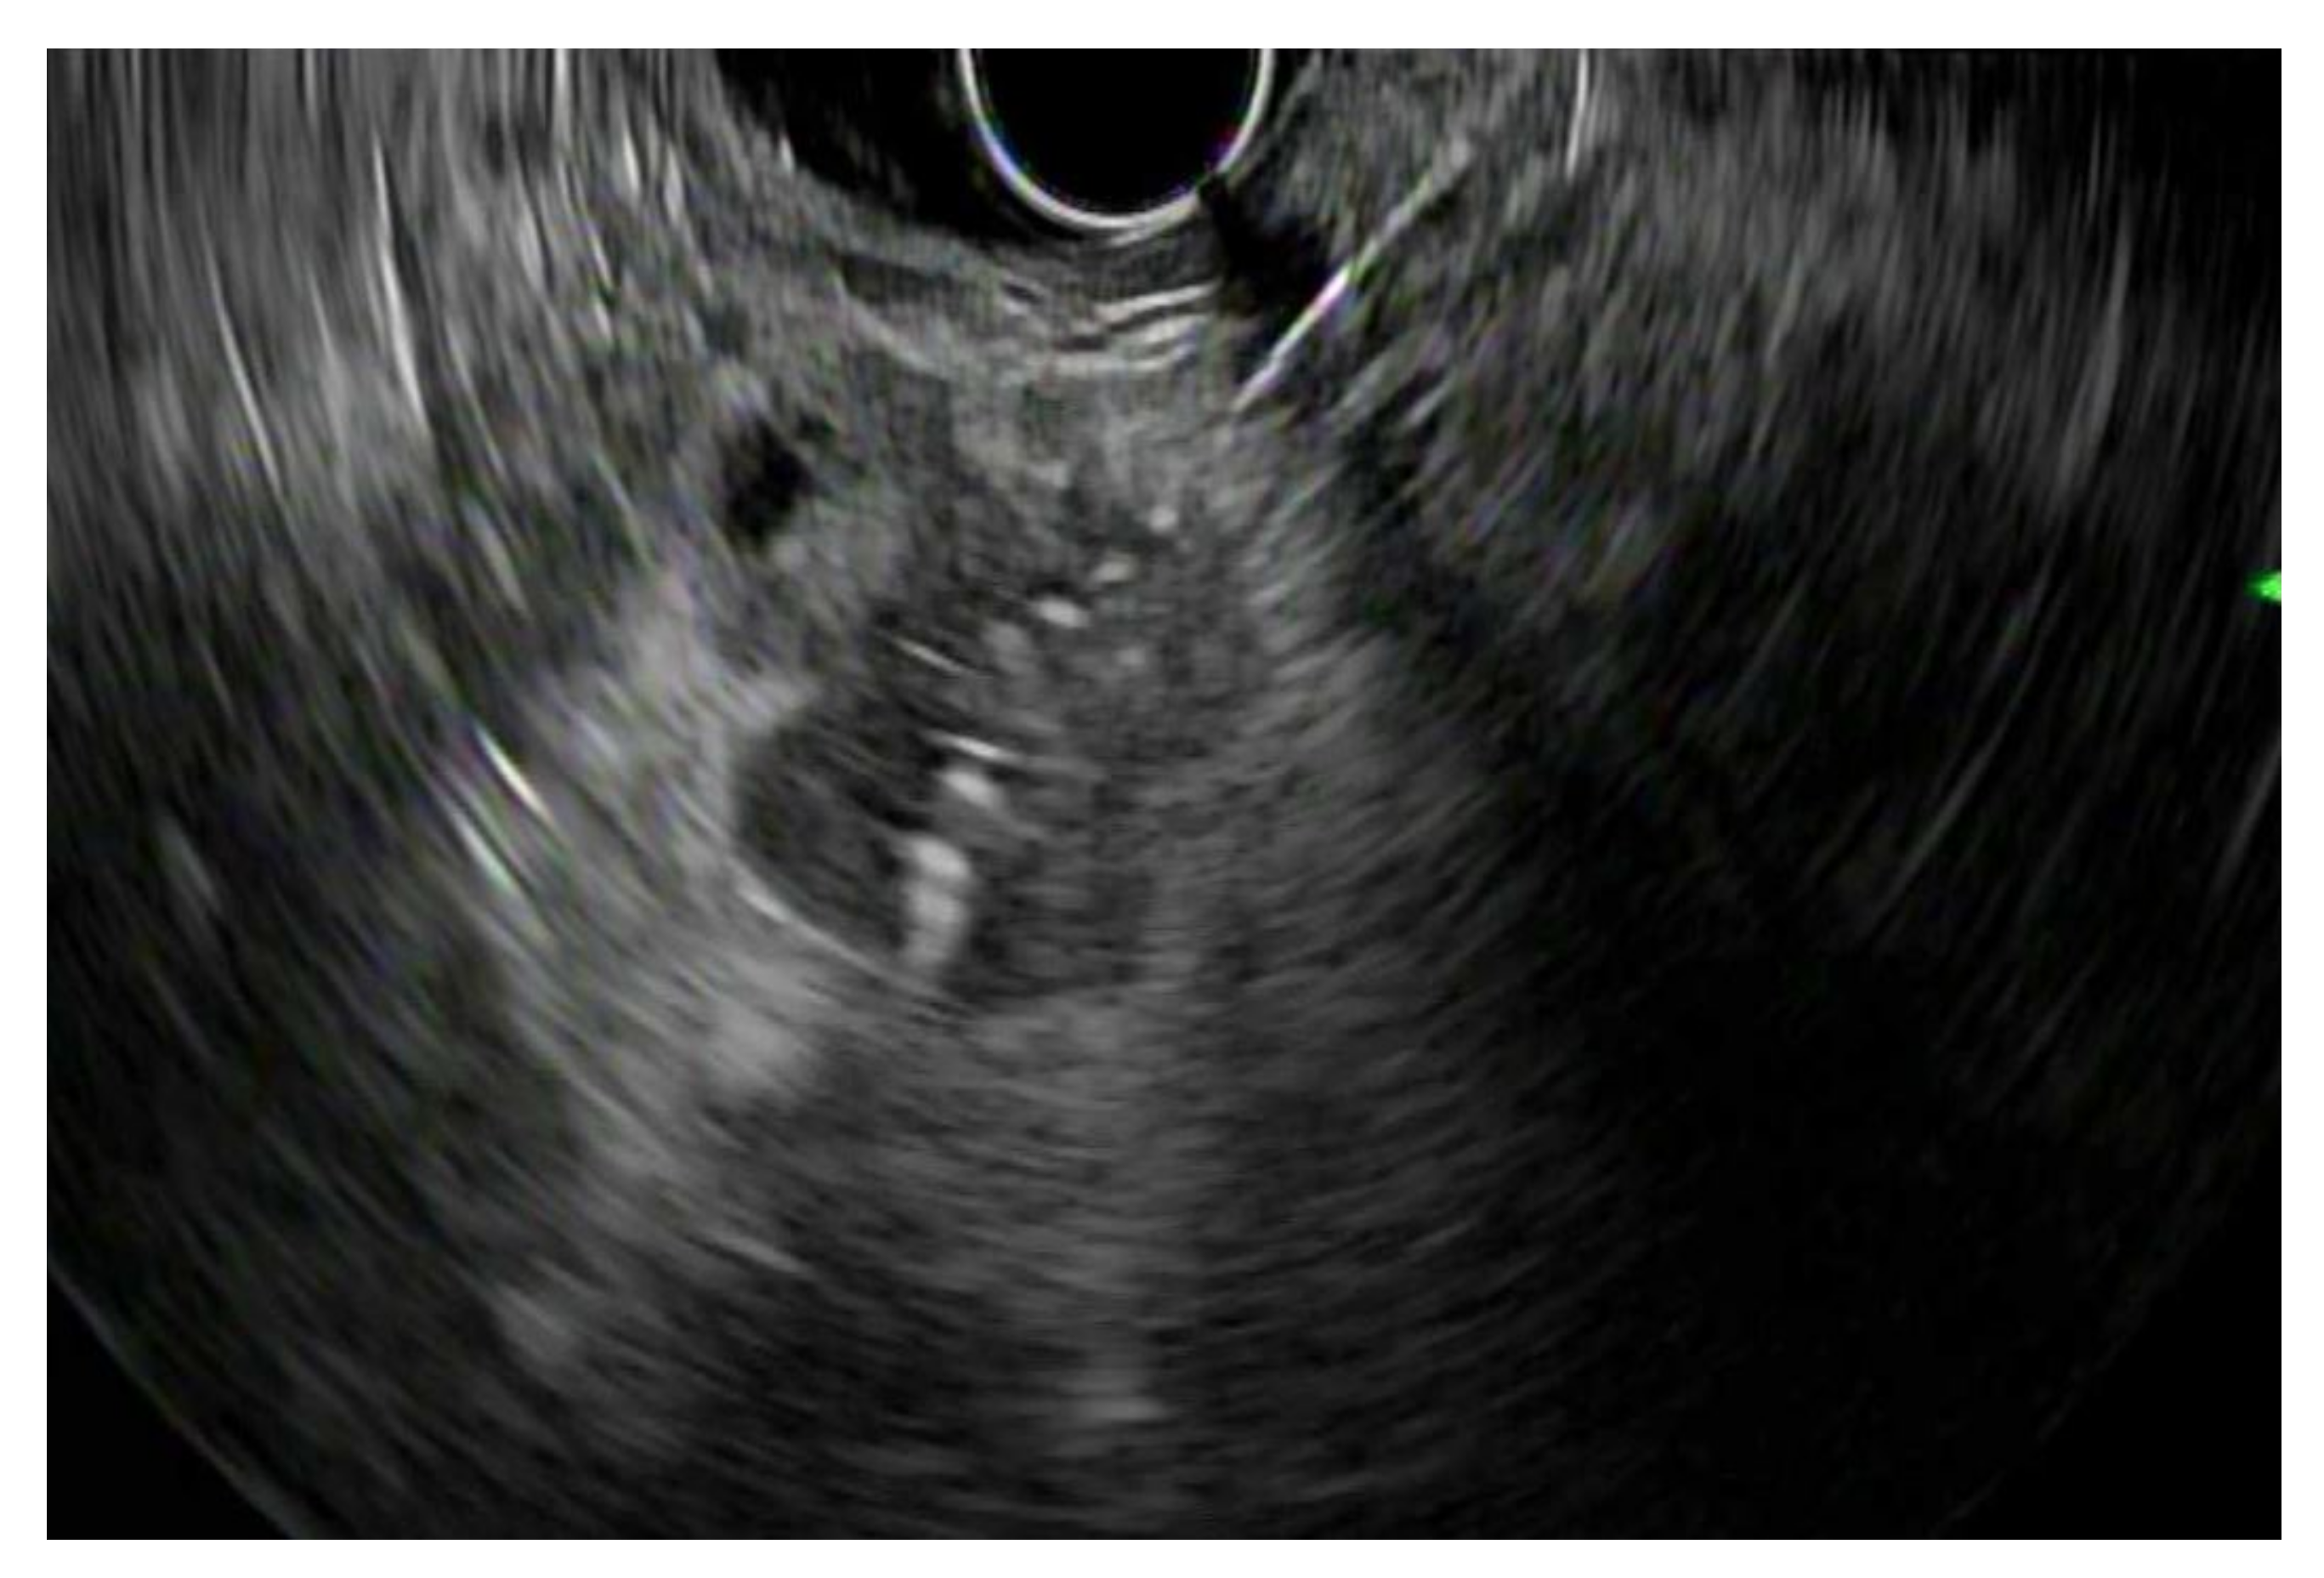

2. Patient Selection and Diagnostic Approach

3. Diagnostic Tests

3.1. EUS vs. Percutaneous Biopsy